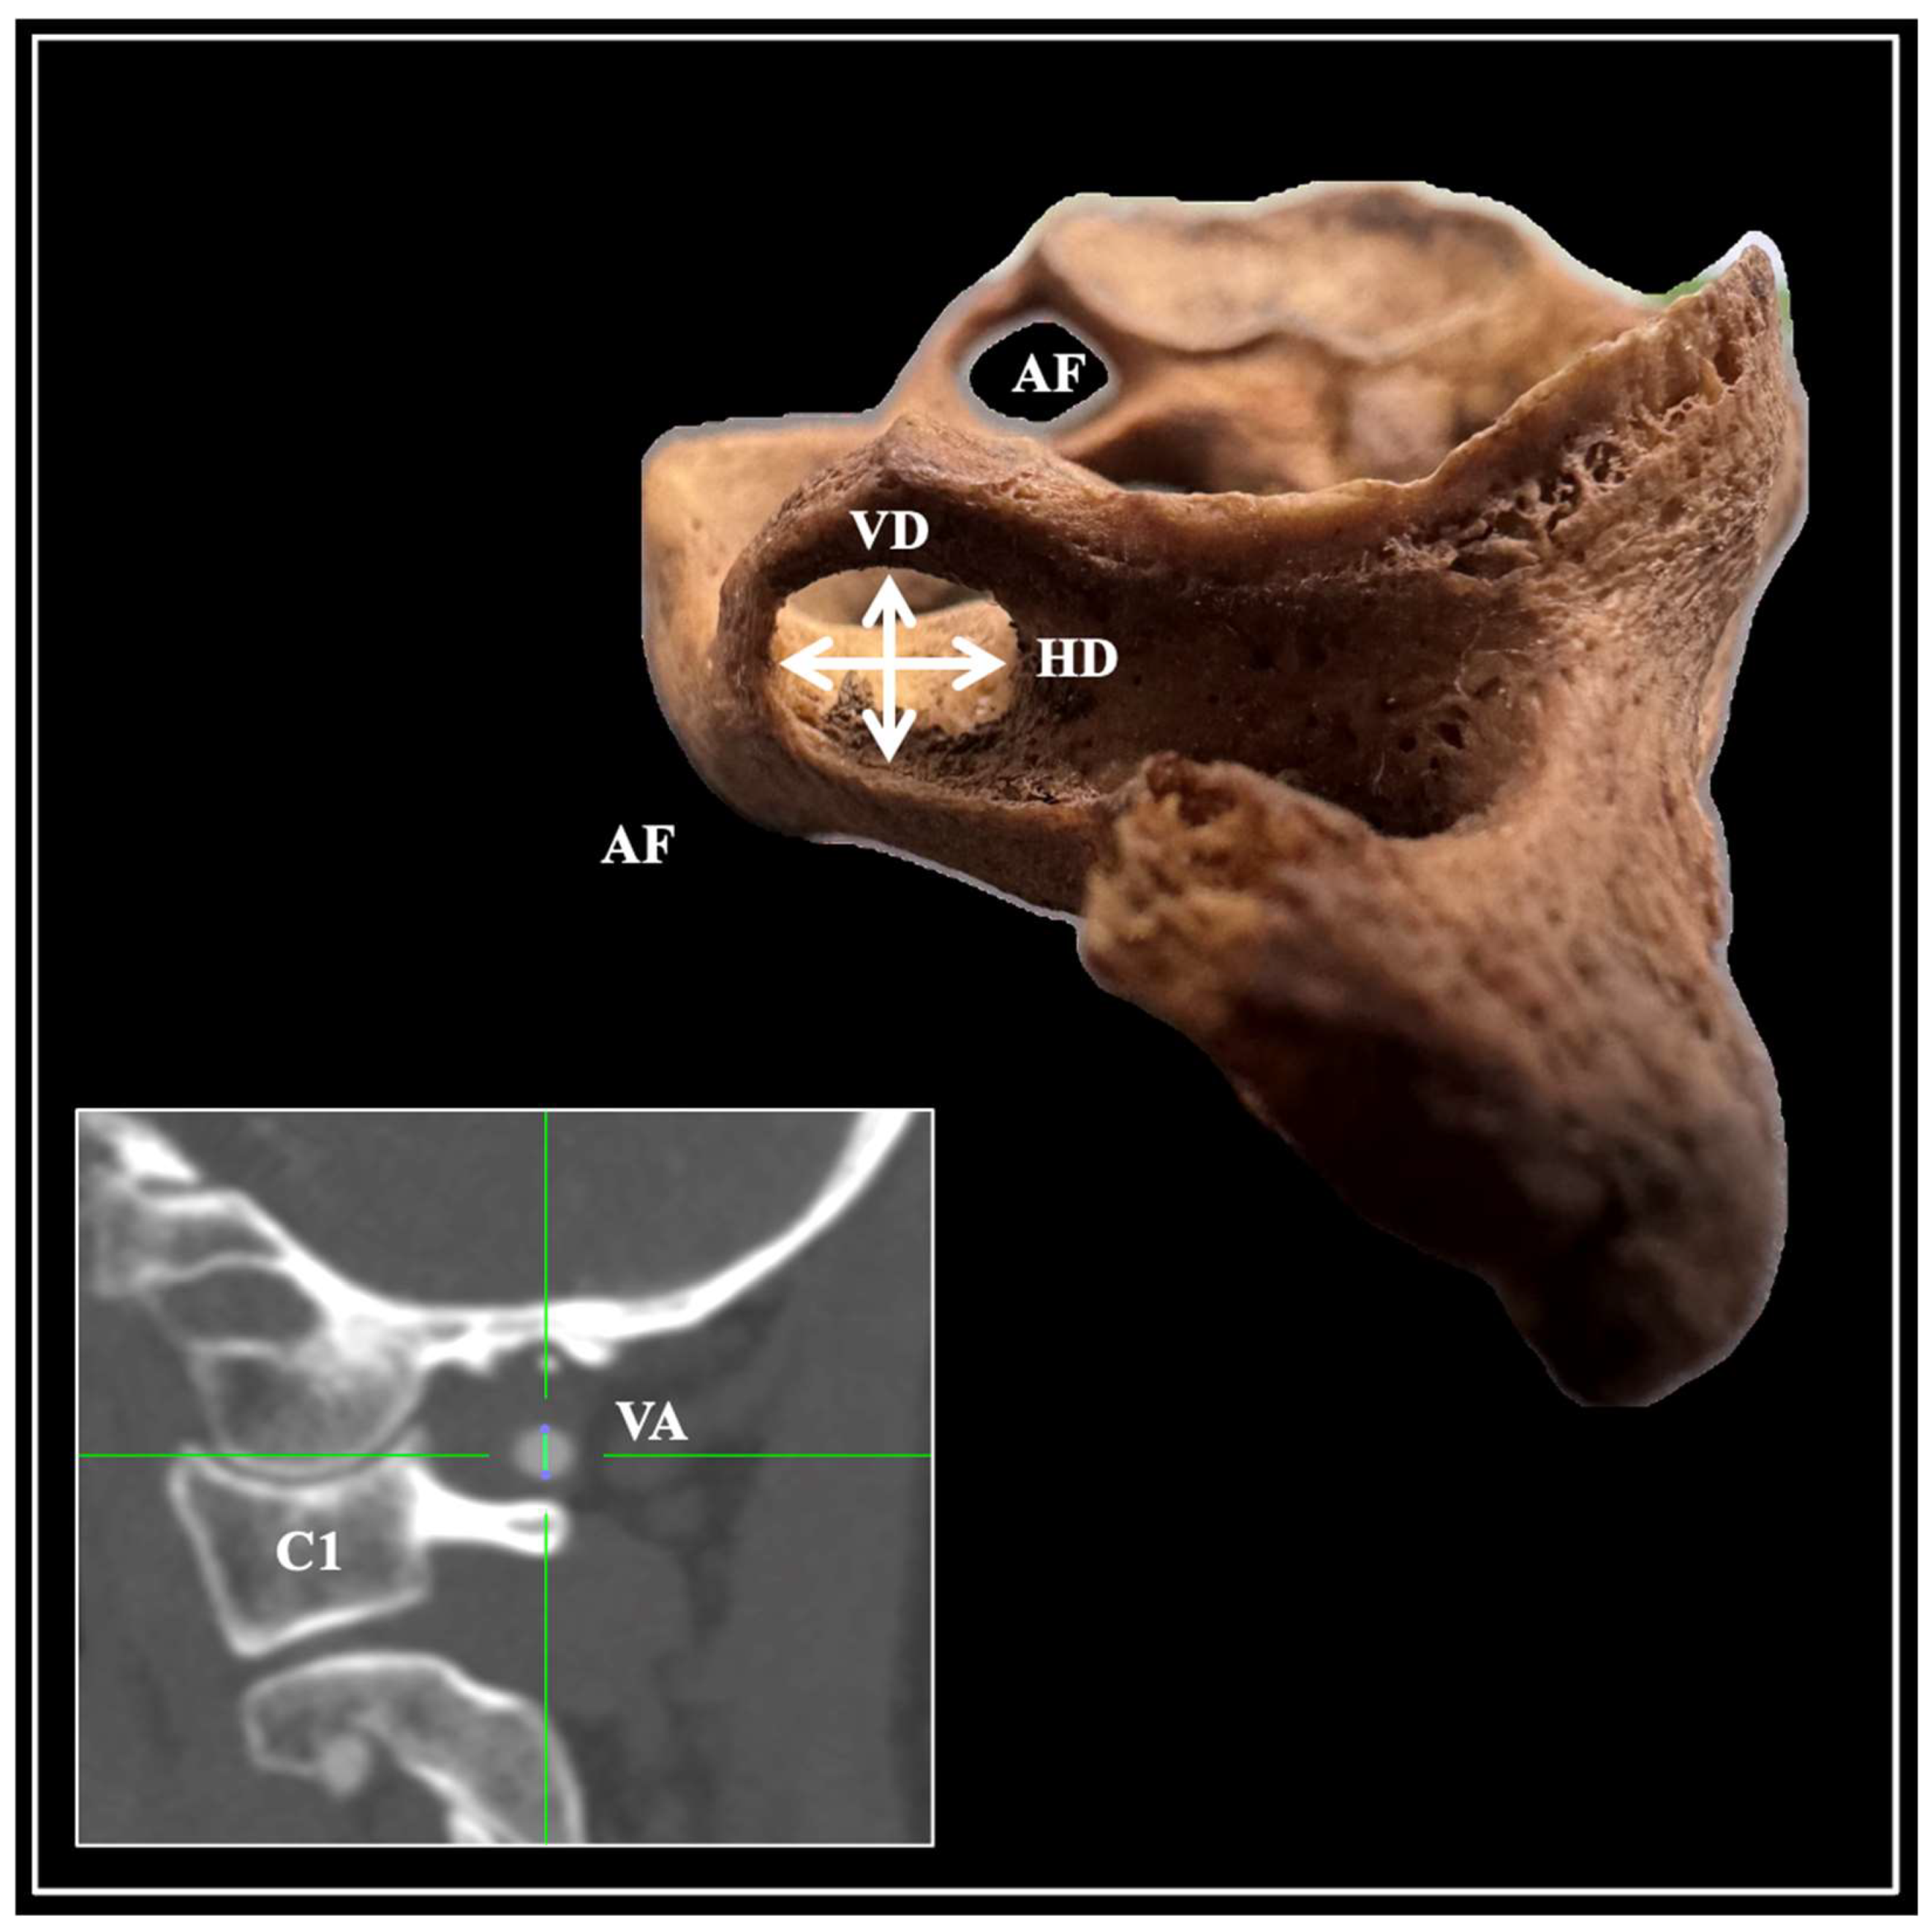

2. Materials and Methods

3. Results

4. Discussion